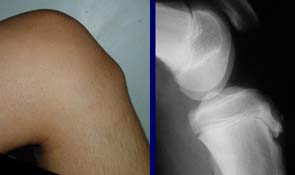

Se caracteriza por un dolor que aparece al realizar actividades físicas como caminar, correr, saltar, justo por debajo de la rodilla, en su parte delantera. Suele provocar inflamación en esa zona, donde apreciaremos un pequeño bulto, y dolor importante al tocarla.

Ante estas patologías relacionadas con el crecimiento es recomendable que el traumatólogo pida una radiografía o una resonancia magnética para estudiar el estado del cartílago de crecimiento.